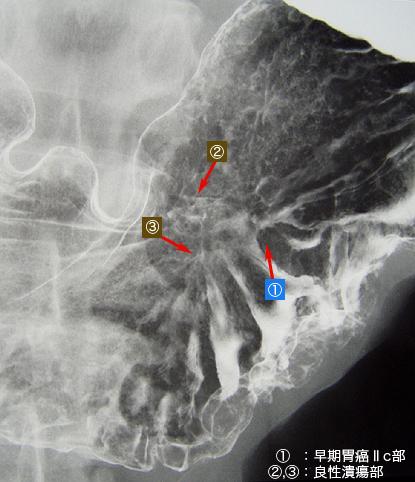

질환(병리주체)의 분류 악성 상피성종양/선암

부위(장기별) 위(부위)/위각

검사방법 X-P

종양의 육안분류 0형(표재형)/IIc형(IIc)

종양의 최대경(밀리미터) 10~14

종양의 심달도 m